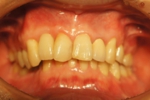

前歯部インプラント骨移植同時症例

大学病院よりご依頼いただいた症例。仮歯が入っていますが、欠損部歯茎が大きくへこんでいて、CT画像ではパノラマレントゲンで想定していたよりもかなり大きく骨がなかったですが、インプラント手術と骨の移植を同時に行い審美的にも回復しました。また同時に行うことにより治療期間が9か月→4か月の短縮されました。被せ物には審美性を考慮して土台からセラミックを使用しました。